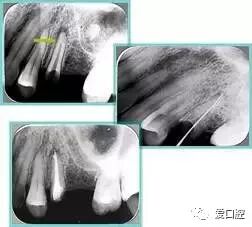

根管初步预备完毕后用 H 锉提拉,之后进行工作长度再确认。插上牙胶尖,拍摄 X 线片,观察主牙胶尖位置。

左图为根管充填术后 X 线片。图中可见,根管充填较好。右下图有白色小点,为侧方加压导致糊剂挤出所致,表明根管充填比较致密。

多根牙时候需进行偏移投照,正位投照无法说明具体哪根牙根管充填效果。